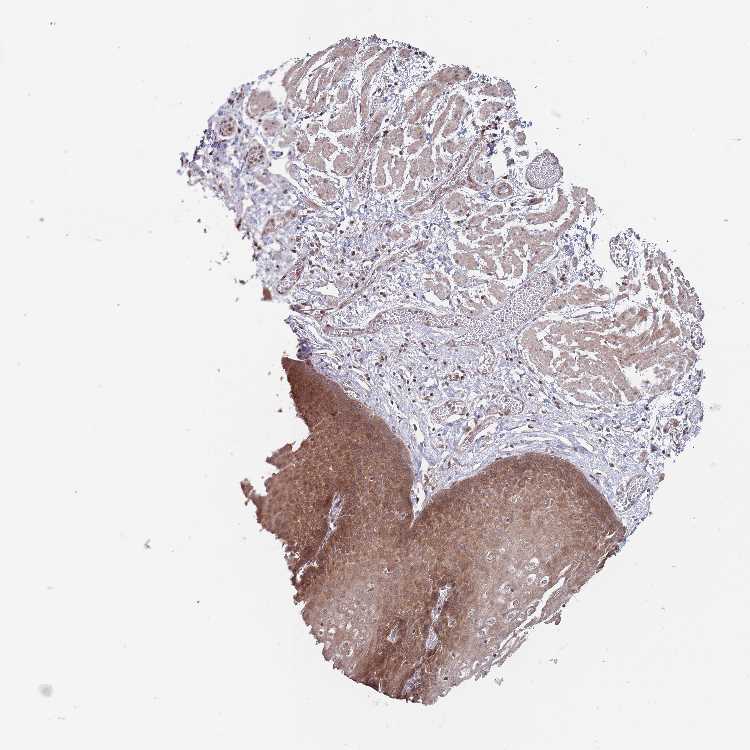

ESOPHAGUS - Antibody stainingi

Antibody staining in the annotated cell types in the current human tissue is reported as not detected, low, medium, or high, based on conventional immunohistochemistry profiling in selected tissues. This score is based on the combination of the staining intensity and fraction of stained cells.

Each image is clickable and will lead to virtual microscopy that enables deeper exploration of all samples and also displays staining intensity scores, fraction scores and subcellular localization as well as patient and tissue information for each sample.

Antibody HPA039228

Squamous epithelial cells High